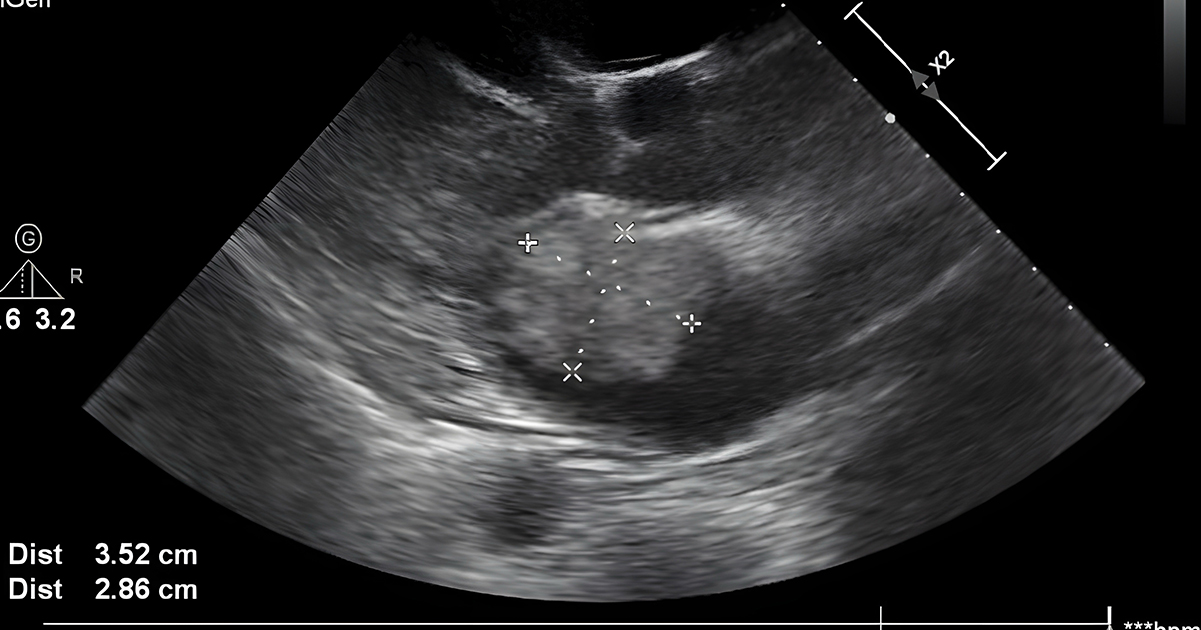

In April 2022, Amanda Foster, now 33, shared an image of an ultrasound with her friends on Facebook, announcing that her unborn son Jay had “healthy kidneys, no cysts and perfect blood flow to and from.”

She added that the boy was “Potter syndrome free,” which according to the Cleveland Clinic is a “rare condition that affects the growth and function of a baby’s kidneys and other internal organs. This condition is life-threatening for the baby and many infants have a short life expectancy.”